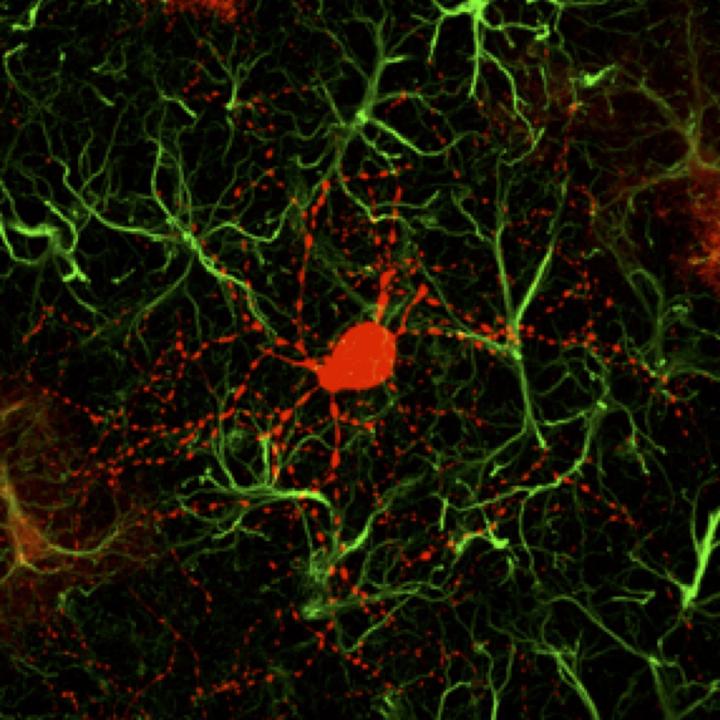

image: This is a a newly converted neuron (red) surrounded by astrocytes (green).